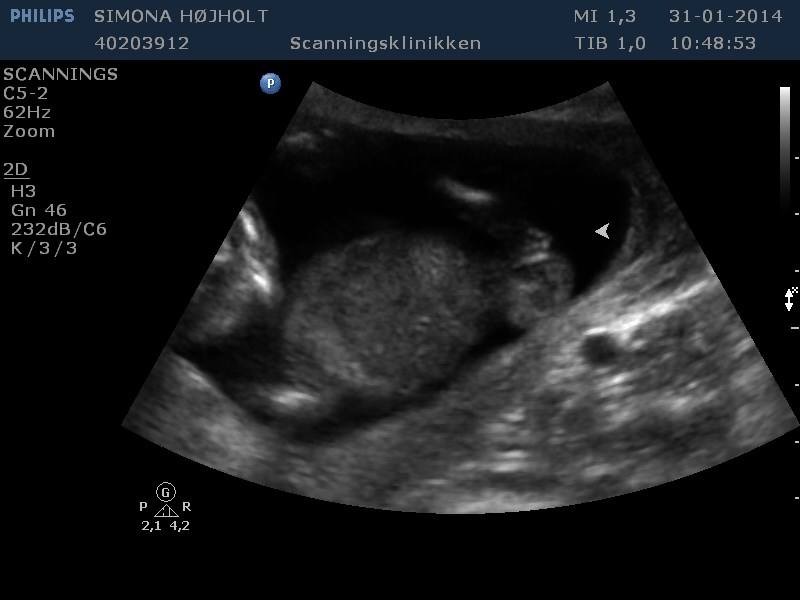

Ja, hvad skal vi have?

Svaret kender jeg, men kan I se det? ;-) Altid godt med lidt træning og gætterier!

Vedhæftede fotos (klik for at se i fuld størrelse)

Umiddelbart synes jeg at kunne se to streger på de nederste to billeder så jeg gætter på en pige